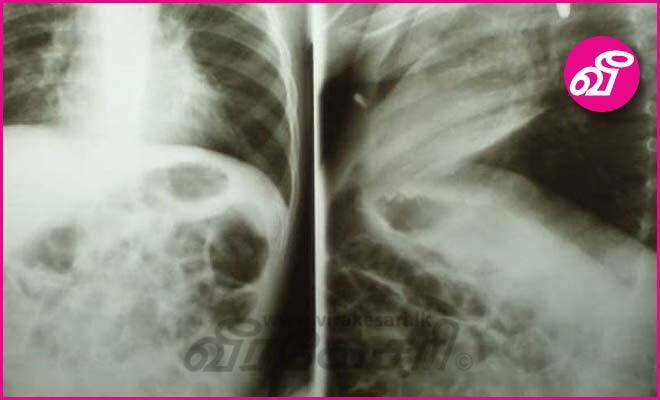

விழுங்கப்பட்ட பற்றரி வெடித்ததால் 2 வயது சிறுவன் உயிருக்குப் போராட்டம்

மெக்ஸிகோவைச் சேர்ந்த 2 வயதான சிறுவனொருவன் விழுங்கிய பற்றரி, வயிற்றுக்குள்  வெடித்ததால் அச்சிறுவன் உயிருக்குப் போராடி வருகிறான்.

அச்சிறுவன்  சுவாசிப்பதற்கு சிரமப்படுவதாகக் கூறி, இச்சிறுவனை அவனின் தாயார் கெனானியா நகரிலுள்ள வைத்தியசாலைக்கு ஒக்டோபர் 23 ஆம் திகதி அழைத்துச் சென்றார்.

அச்சிறுவன் பற்றரியை விழுங்கியிருப்பதை மருத்துவர்கள் கண்டுபிடித்தனர். அதன்பின், ஹேர்மோசிலோ நகரிலுள்ள வைத்தியசாலைக்கு அச்சிறுவன் அனுப்பப்பட்டான்.

அச்சிறுவனை சத்திரசிகிச்சைக்கு உட்படுத்துவதற்கு முன்னர், அந்த பற்றரி வெடித்துவிட்டதாகவும், இதனால், சிறுவனின் உடல்நிலை மேலும் மோசமடைந்துள்ளதாகவும் செய்தி வெளியாகியுள்ளது.